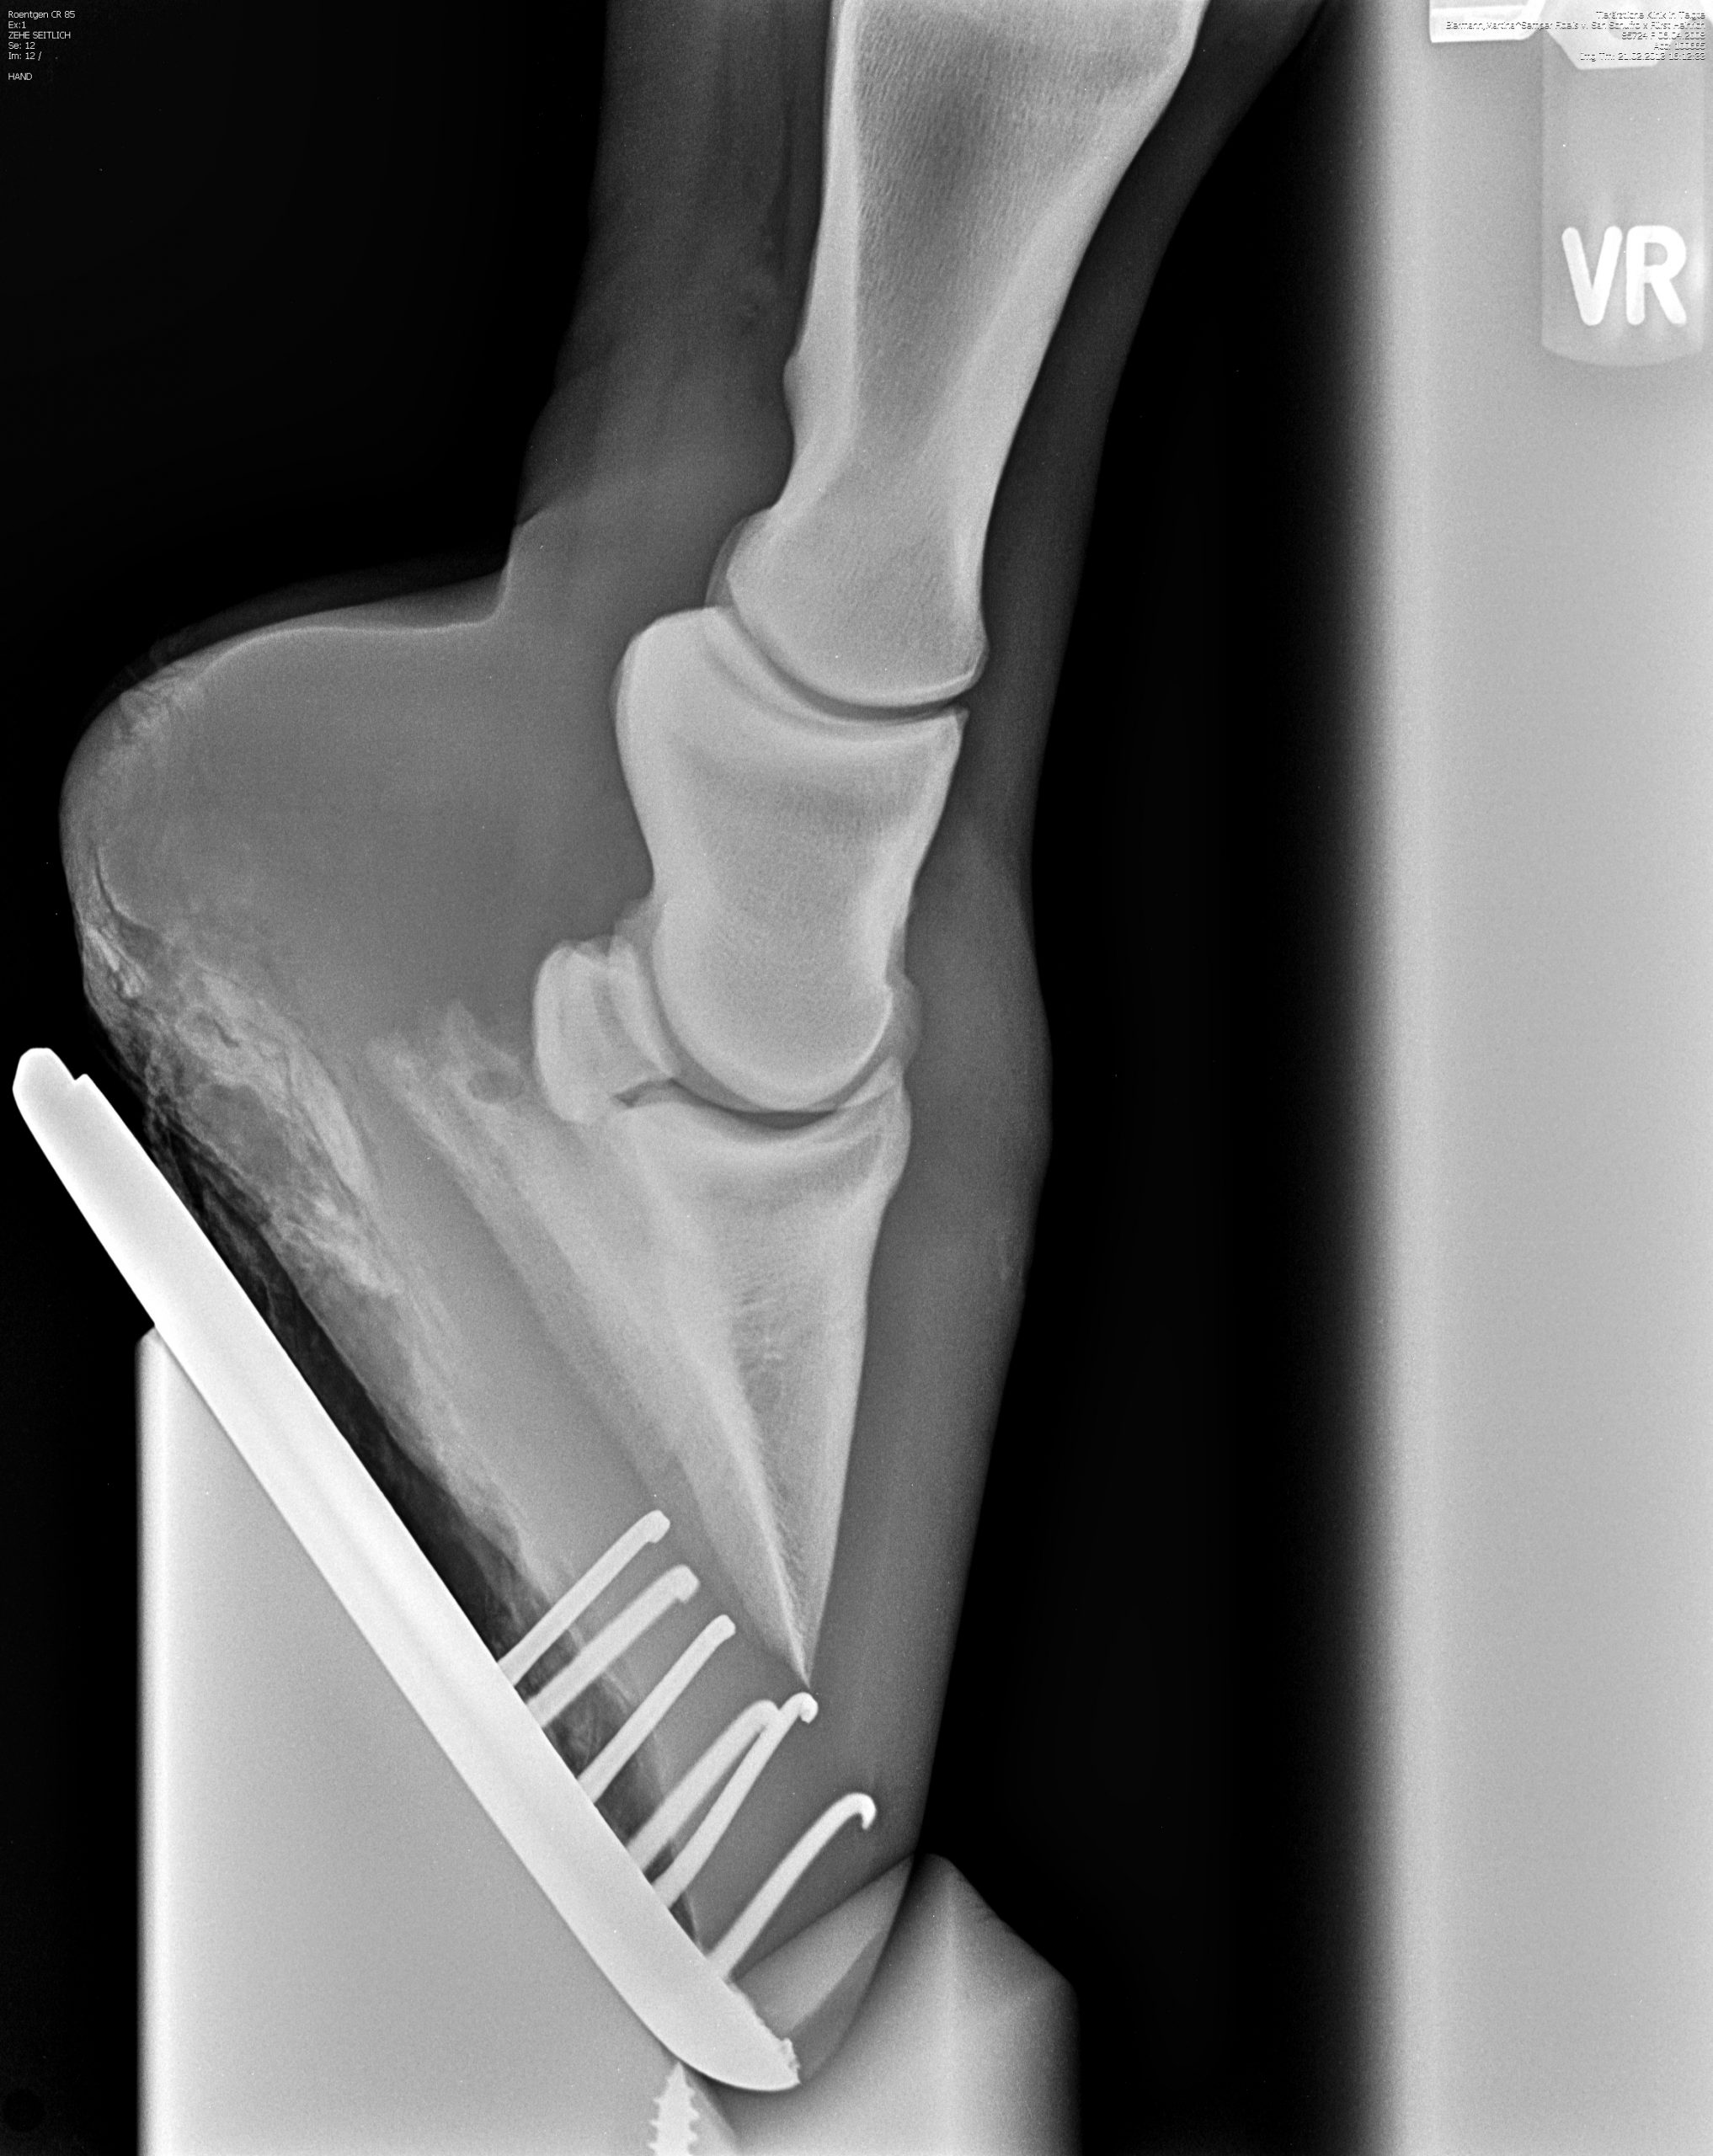

Röntgenbilder

Diese Sammlung zeigt verschiedene Röntgenaufnahmen, die eine Vielzahl von anatomischen Strukturen und potenziellen Gesundheitszuständen veranschaulichen. Jede Aufnahme bietet wertvolle Einblicke in die Gesundheit und das Wohlbefinden Ihrer Pferde.